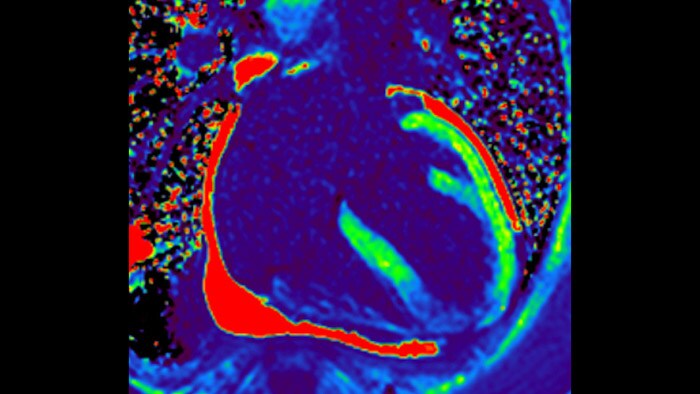

La utilidad diagnóstica y pronóstica de la RM cardíaca está aumentando. Evaluar la anatomía y función del corazón mediante adquisiciones cinematográficas, adquirir información sobre perfusión y viabilidad del tejido cardíaco, visualizar posibles edemas con secuencia de sangre negra, acceder e incluso cuantificar la caracterización tisular con CardiacQuant.

IntelliSpace Portal MR Caas(7,8) Strain(9) ayuda en el diagnóstico y monitoreo del paciente al proporcionar parámetros de deformación global como la deformación longitudinal global (GLS), la tensión circunferencial global (GCS) y la tensión radial global (GRS), mediante imágenes de RM de eje corto y largo, así como también al describir la deformación del miocardio, como el acortamiento, el engrosamiento y el alargamiento durante el ciclo cardíaco.